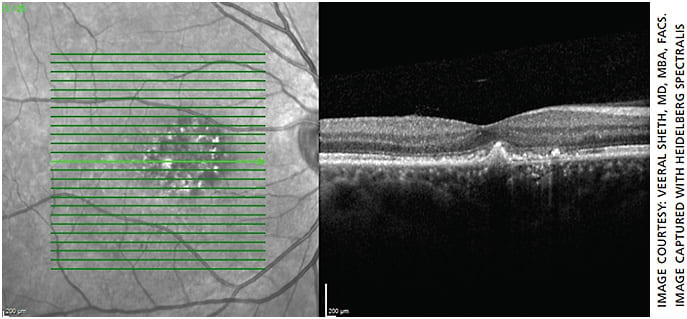

Similarly, Veeral Sheth, MD, MBA, FACS, partner & director of clinical trials, University Retina, with offices in the Chicago area, has used micropulse laser to treat patients with DME and CSCR (Figures 1-7). However, he notes, over the past decade he has used micropulse laser somewhat less for patients with DME and more for patients with CSCR. That’s because of the efficacy and safety profile of intravitreal injections for DME.

“The only quantification you have is when they follow up and you do an OCT and you see that there’s been improvement,” says Dr. Sheth.

One key to success is administering confluent treatment, notes Dr. Sheth. In traditional laser, he points out, you’re burning tissue and thus need to keep the spots fairly separated. With micropulse laser, “you’re able to actually cover an area more confluently and therefore treat more densely without the concern of burning or damaging tissue.”

“This dense or confluent treatment I think is critical,” he adds. “I think it’s something that physicians, especially early on with their use, don’t do, because they’re fearful, because it’s not traditionally how we do focal laser. The problem is, then you run the risk of not having optimal results. If you do a little bit more of this confluent type of treatment, you’re going to get better results.”